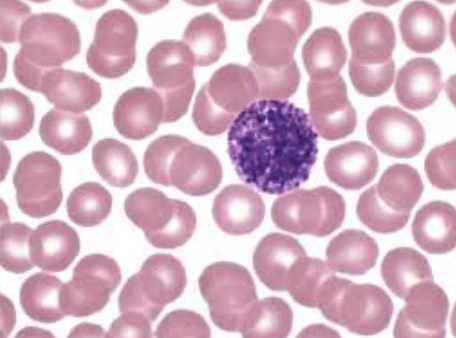

Lymphocyte

[Function of a] Lymphocyte

Mount immune response by direct cell attack of via antibody production

Order of Leukocytes from most numerous to least numerous

Neutrophil --> Lymphocyte --> Monocyte --> Eosinophil --> Basophil

(Never Let Monkeys Eat Bananas)